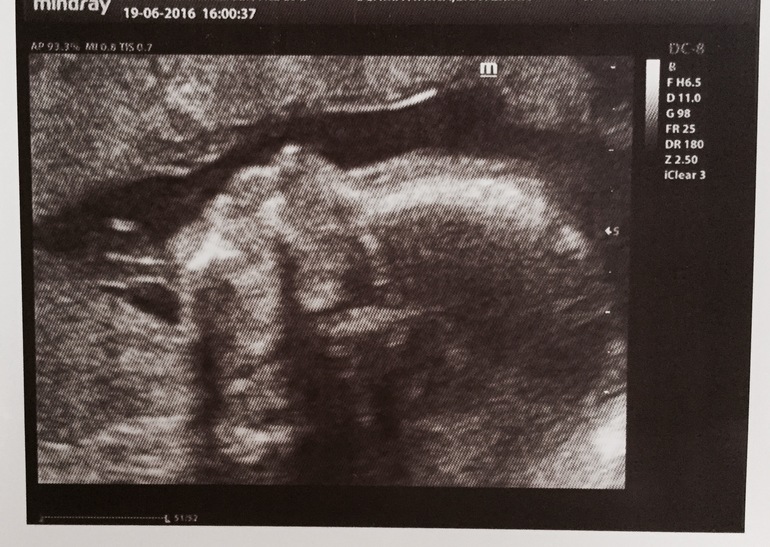

18+5. 2 скрининг.

весь процесс наблюдали на отдельном экране на стене как и в прошлый раз. по результатам имеем детеныша 24см роста/260гр веса с огромными мужицкими причендалами, кружку моему быть отныне синим🔵 Как уж все вокруг не били себя пяткой в грудь, утверждая, что будет девочка и никак иначе, парень показал всем большую.. Ага, фигу, ее самую) все показатели соответствуют сроку, нос в норме, руки-ноги дрыгаются, голова вертится, расщелин неба нет, весь внутренний мир на месте, ну и прочие традиционные для второго скрининга трали-вали. Плацента подползла повыше, диагноз предлежание снят, отмашка на секс получена. шейка 33мм. По итогу как обычно диск с записью всего узи, фотки на холодильник. Парень становится сильнее с каждым днем, толкается в одно и то же место, чую скоро дыра там будет) так что, растем дальше)